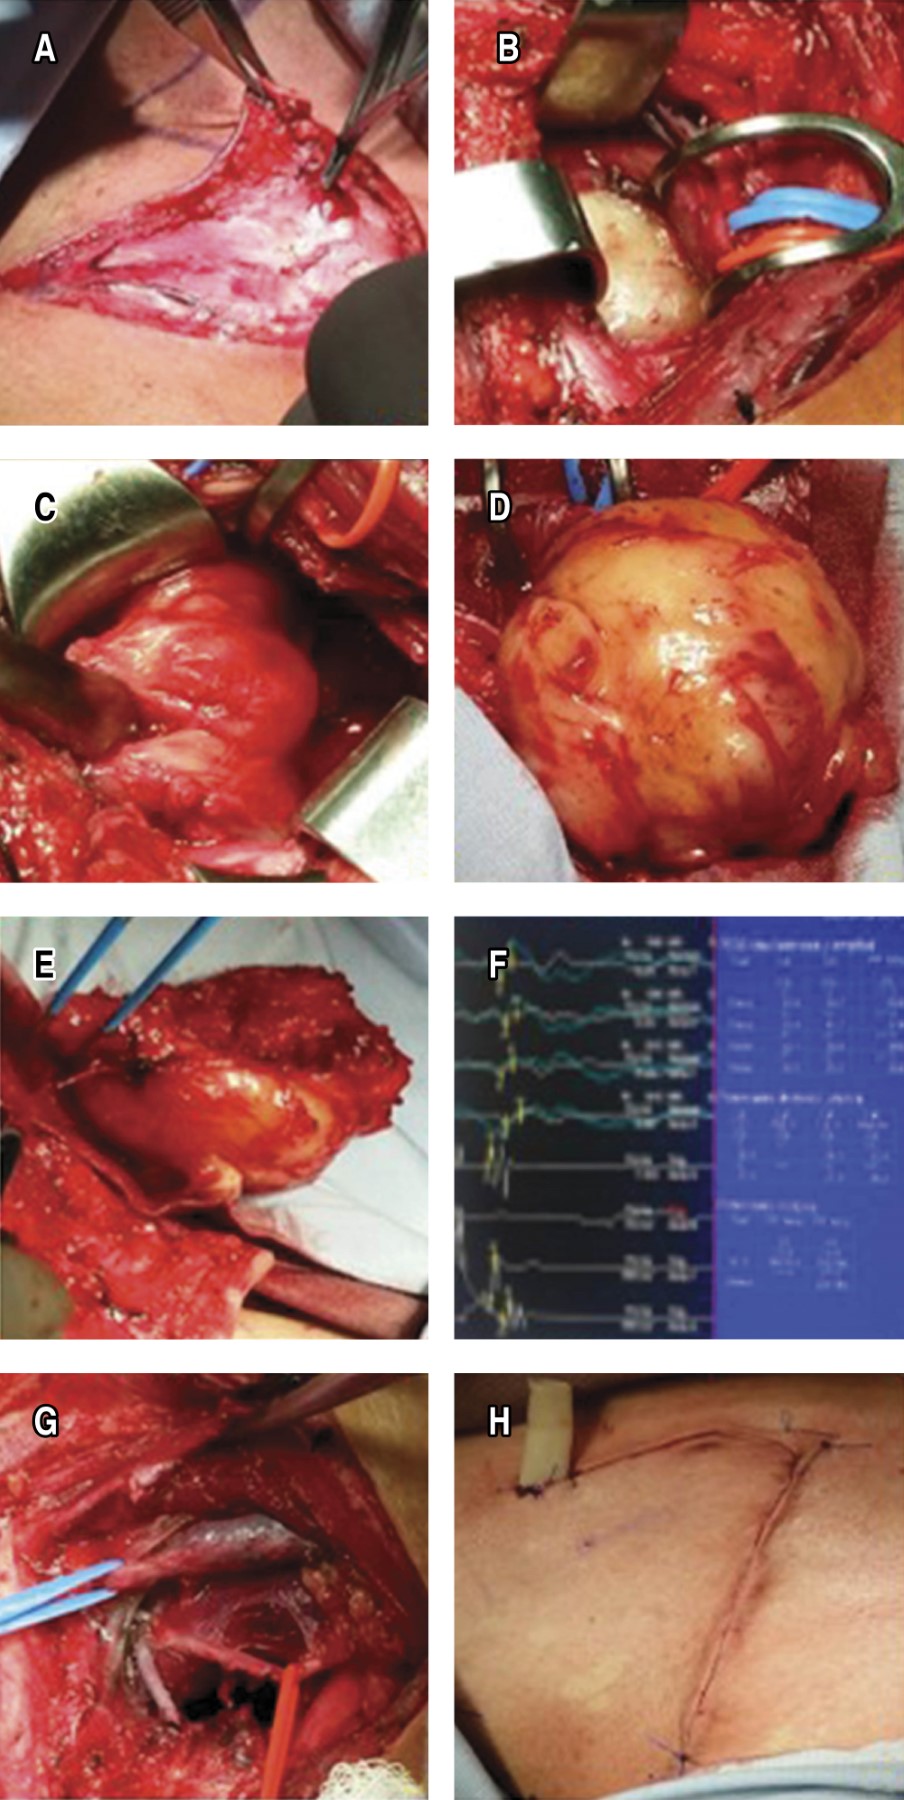

Tumor excision was performed through anterior cervicothoracic approach with neurophysiological monitoring, finding: spherical mass of 9 × 7 × 5 cm and encapsulated, resected by central and intracapsular enucleation dependent on C5, C6 and C7 nerve roots, extrapleural corroborated by a left thoracoscopic approach, without drains.

The pathology report is a diagnosis of cervicothoracic schwannoma. At two weeks' post-surgery, the patient had recovered mobility but continued with significant atrophy; however, he presented gradual recovery of muscle tone and strength and movement in the affected limb at seven years of follow-up with rehabilitation support (Figure 2A-H).

The causes of postoperative neurological deficits are related to preoperative nerve compression, mechanical injury or transoperative ischemia, reoperations associated with incomplete enucleation. Therefore, several perioperative neurological monitoring methods have been developed, such as spontaneous electromyography (EMG), somatosensory evoked potentials (SEP) and nerve action potentials (NAP).8 With EMG, nerve stimulation is performed and muscle activity is recorded to identify or avoid nerve damage; with SEP, it is useful for recording brachial plexus lesions and evaluates whether there is continuity with the central nervous system; with NAP, the nerve trunk proximal to the lesion area is directly stimulated and a recording is obtained in the area distal to the lesion; it is useful in nerve lesions due to continuity and determines the need for other reconstruction procedures with sural nerve grafts. The critical steps in surgical resection of brachial plexus schwannoma with electrophysiological monitoring in our case were: a) exposure of the nerve proximal and distal to the tumor by neurolysis; b) capsular exposure and electrostimulation of the tumor to localize and map the functional nerve distribution; c) longitudinal incision of the capsule in the direction of adjacent nerves with no recordable functional activity; d) enucleation and electrostimulation to avoid damage to functional nerve fibers; e) final exposure of the proximal and distal poles of the tumor where the nerves run and evaluation by NAP to determine a potential continuity injury requiring reconstruction with sural graft; and f) postoperative monitoring of basal and functional deficits for future rehabilitation and prognosis.

The schwannoma, in our case, facilitated surgical separation of healthy and functional nerve fibers; neurorrhaphy or sural grafting was not necessary as described for neurofibromas and primary malignancies; the anterior cervicothoracic approach with an L-shaped incision was sufficient. However, the cervico transsternal trap-door approach should be considered for invasive masses with a large intrathoracic and mediastinal component.9,10